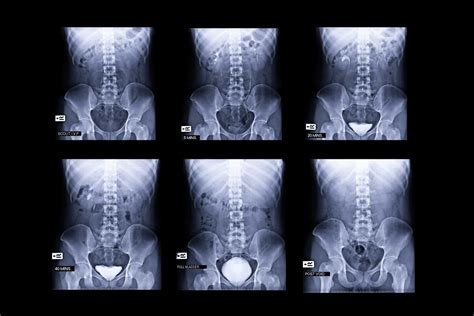

A Ct Scan IVP (Intravenous Pyelogram) is a sophisticated imaging study that allows radiologists to map out the entire urinary system. Unlike a standard X-ray, which provides a flat image, the CT scan captures cross-sectional slices of your body. When the contrast medium is injected intravenously, it travels through your bloodstream to the kidneys and is eventually excreted into the ureters and bladder. This process highlights any blockages, structural abnormalities, or functional issues that might be causing you discomfort.

Doctors typically order this scan if they suspect conditions such as:

• Kidney stones or ureteral calculi.

• Blood in the urine (hematuria).

• Tumors or cysts within the urinary tract.

• Congenital anomalies or structural defects.

• Recurring urinary tract infections.